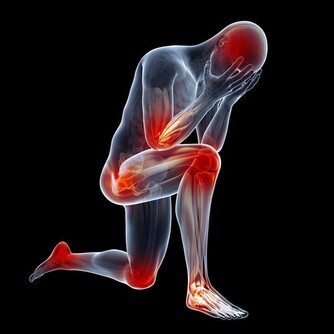

什麼人不適合吃香蕉? 1:體質偏虛寒者 香蕉性寒體質偏虛寒者最好避之則吉,像胃寒、虛寒、腎炎、也不要吃香蕉,以上幾種病人如果吃香蕉也不利於身體的健康。還有點懷孕期腳腫的患者,也最好是不要吃香蕉。 2:空腹的人 香蕉是可以促進胃腸道蠕動的,如果空腹吃就會造成腸胃的提前工作,長期空腹吃香蕉也不利於身體的健康。為什麼不能空腹吃香蕉呢,因為空腹時腸胃中幾乎沒有可提供消化的食物,在空腹時吃香蕉就會加快腸胃的運動,促進血液的循環,增強心臟的負荷,容易導致心肌梗塞。 3:關節炎患和糖尿病患者 香蕉的含糖量是比較高的,會使血液循環減慢,代謝物堆積,如果關節炎和糖尿病患者不應該吃香蕉,否則會加重病情。 4:腎炎患者 腎炎患者也是不可以吃香蕉的,因為香蕉中含有大量的鉀、鎂元素,腎炎患者的派濾功能比較差,香蕉會使血液中的鈣鉀鎂比例失調,進而促進腎病的加重,所以腎病寒者最好是不要吃香蕉。